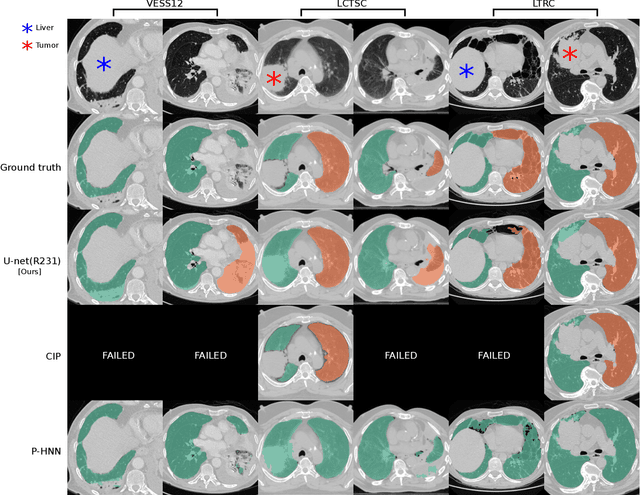

Abstract:Automated segmentation of anatomical structures is a crucial step in many medical image analysis tasks. For lung segmentation, a variety of approaches exist, involving sophisticated pipelines trained and validated on a range of different data sets. However, during translation to clinical routine the applicability of these approaches across diseases remains limited. Here, we show that the accuracy and reliability of lung segmentation algorithms on demanding cases primarily does not depend on methodology, but on the diversity of training data. We compare 4 generic deep learning approaches and 2 published lung segmentation algorithms on routine imaging data with more than 6 different disease patterns and 3 published data sets. We show that a basic approach - U-net - performs either better, or competitively with other approaches on both routine data and published data sets, and outperforms published approaches once trained on a diverse data set covering multiple diseases. Training data composition consistently has a bigger impact than algorithm choice on accuracy across test data sets. We carefully analyse the impact of data diversity, and the specifications of annotations on both training and validation sets to provide a reference for algorithms, training data, and annotation. Results on a seemingly well understood task of lung segmentation suggest the critical importance of training data diversity compared to model choice.